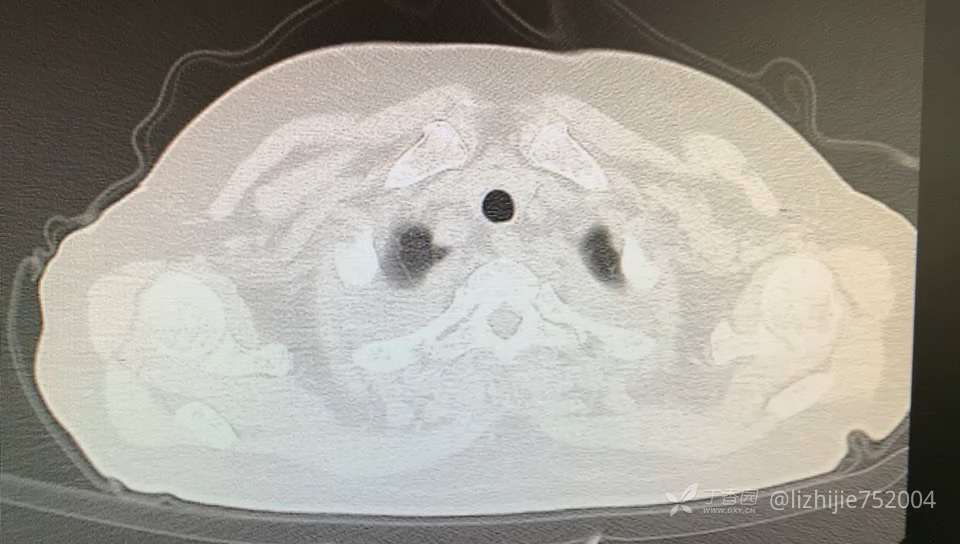

63岁女性,农民,无粉尘接触史。主因:咳嗽、咳痰2月余,呼吸困难半月。痰液不多,为少许白色黏痰,不伴发热、咯血、胸痛等其它症状。既往有冠心病史,发现糖尿病2月。入院动脉血气示I型呼吸衰竭。CT如下: